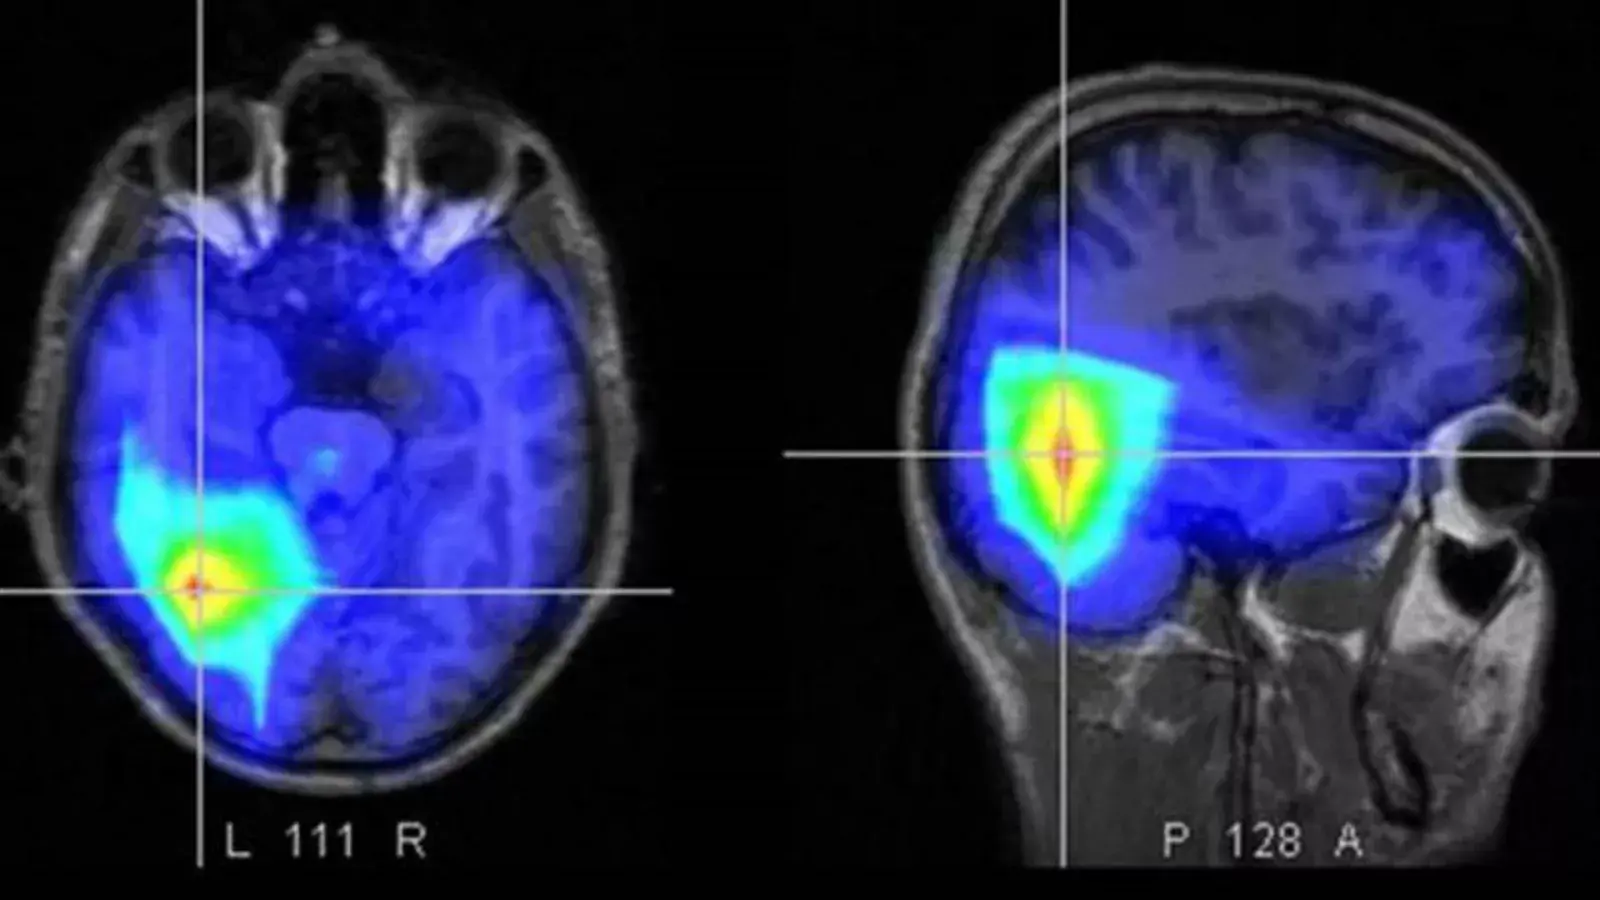

Más adelante, ahondó sobre cómo va evolucionando su recuperación: "Solo el equilibrio tengo que ir recuperando pero, fue un ACV fuertísimo, infarto cerebral o infarto isquémico. Tengo una cosita en el corazón que después tengo que operar y estoy agradecido. Quiero agradecer el amor que sentí".

“Tuvo que ser internado debido a un cuadro de mareos y presión alta. Luego de realizarle estudios de rutina, se pudo constatar que el cantante sufrió un accidente cerebrovascular, producto del estrés”. decía el comunicado de la banda en su cuenta oficial de Instagram.